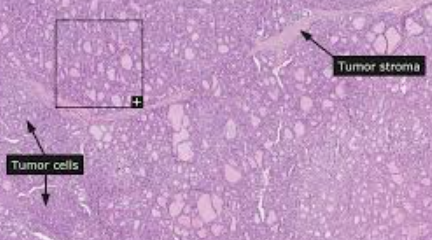

갑상선암에는 유두상 갑상샘암, 여포상 갑상샘암, 갑상선 수질암, 역형성 갑상샘암 등 여러 종류가 있습니다. 각 유형은 암이 발생하고 독특한 특성과 행동을 보이는 갑상선 내의 특정 세포의 이름을 따서 명명되었습니다. 조기 진단으로 완치율을 높이기 위해 아래의 갑상선암 증상을 알아두는 것이 중요합니다.